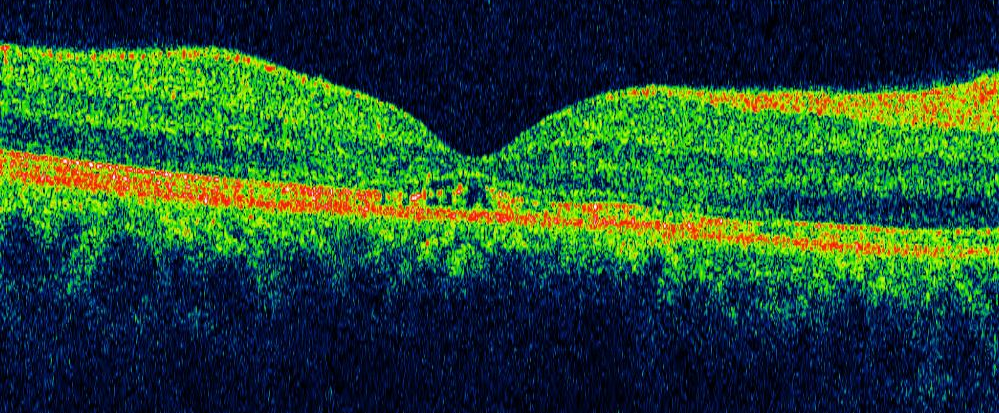

Presso i centri Oculistico / Ortottico di Firenze e Pisa è possibile prenotare esami diagnostici oculari come:

- OCT;